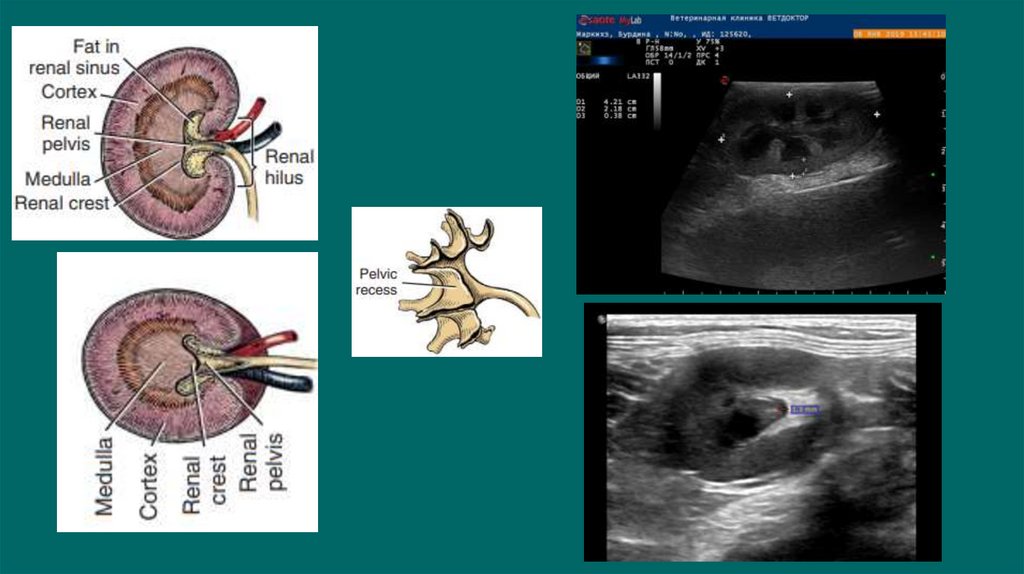

Новообразования мочевого пузыря

Сосудистая сеть почек

19. Ультразвуковое исследование

Можем обнаружить рентгенпрозрачные уролиты ,оценивать архитектуру

почки, паранефральные ткани, ретроперитониальные ткани, кисты

,инфартуи ы почек, изменение эхогенности, неоплазию, расширение

почечных лоханок и мочеточников, измерить толщину стенки мочевого

пузыря, визуализировать свободную жидкость в брюшной полости

УЗИ мониторинг изменений картины мочевой системы

• размер уретры

• размер лоханки и мочеточников

• количество свободной жидкости